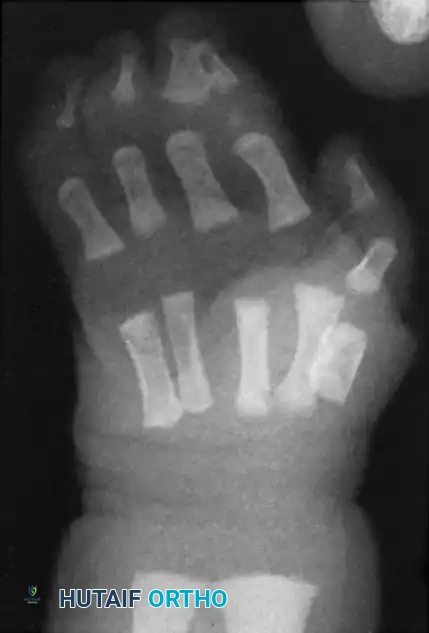

Fig. 76-33 Simple syndactyly. Fingers are bridged only by skin and other soft tissues. A, Palmar view. B, Dorsal view. C, Radiograph. Note the angular deformity of the ring finger.

Fig. 76-34 Complex syndactyly. Common bony elements are shared by the involved fingers, necessitating precise osteotomies during separation.